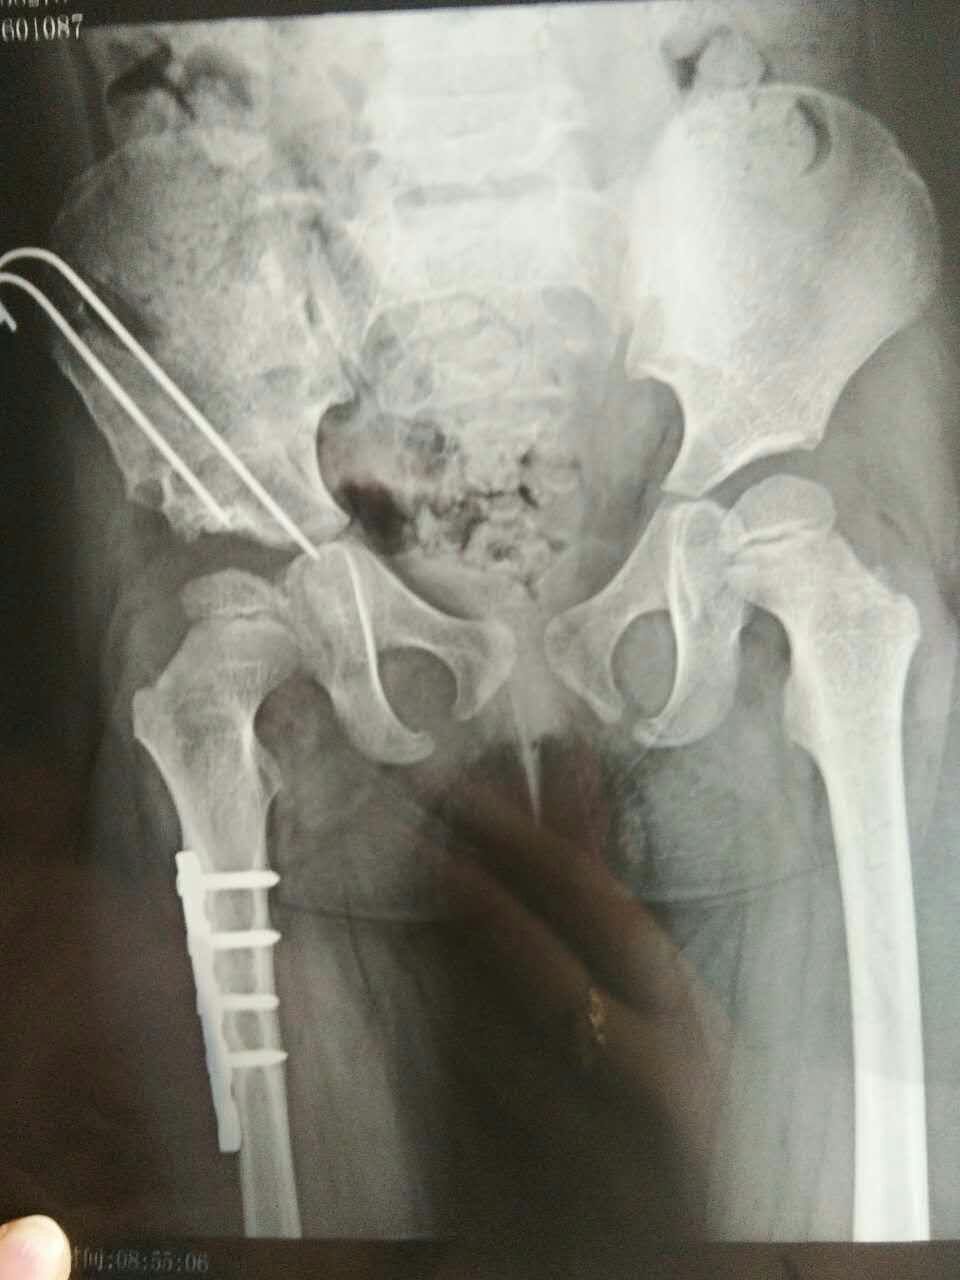

即时求助左髋关节脱位并髋臼骨折目前治疗方案是否需要手术昨天术后

图片尺寸1536x2048